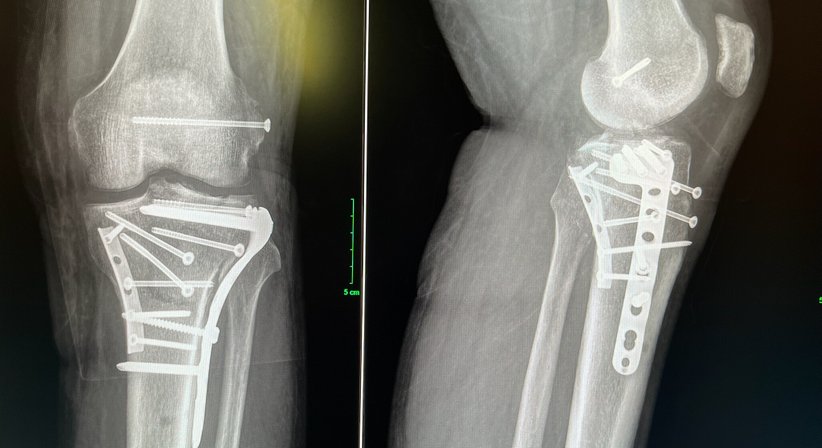

Knochenbrüche der unteren Extremität:

Schenkelhalsbruch, hüftnahe Frakturen, Oberschenkelbruch, Frakturen im Bereich des Kniegelenkes, Unterschenkelbruch, Knöchelbruch, Verletzungen im Fussbereich